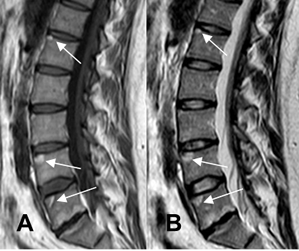

Fig 59 F. Espondilitis anquilosante.

A: Rx lateral. Se identifican sindesmofitos, en la parte anterior de los cuerpos vertebrales y esquinas densas.

B: RM sagital en T1 y C: RM sagital en T2. Lesiones Romanus en la parte anterior de los cuerpos vertebrales, hiperintensas en ambas secuencias, por evolución subaguda.

Fig 59 G. Lesiones Romanus.

A: RM sagital en T1, B: RM sagital en T2 y C: RM sagital en STIR. Múltiples lesiones Romanus, en las esquinas de los cuerpos lumbares. Son hiperintensas en T1 y T2 y suprimen en STIR, por depósito graso de evolución subaguda.